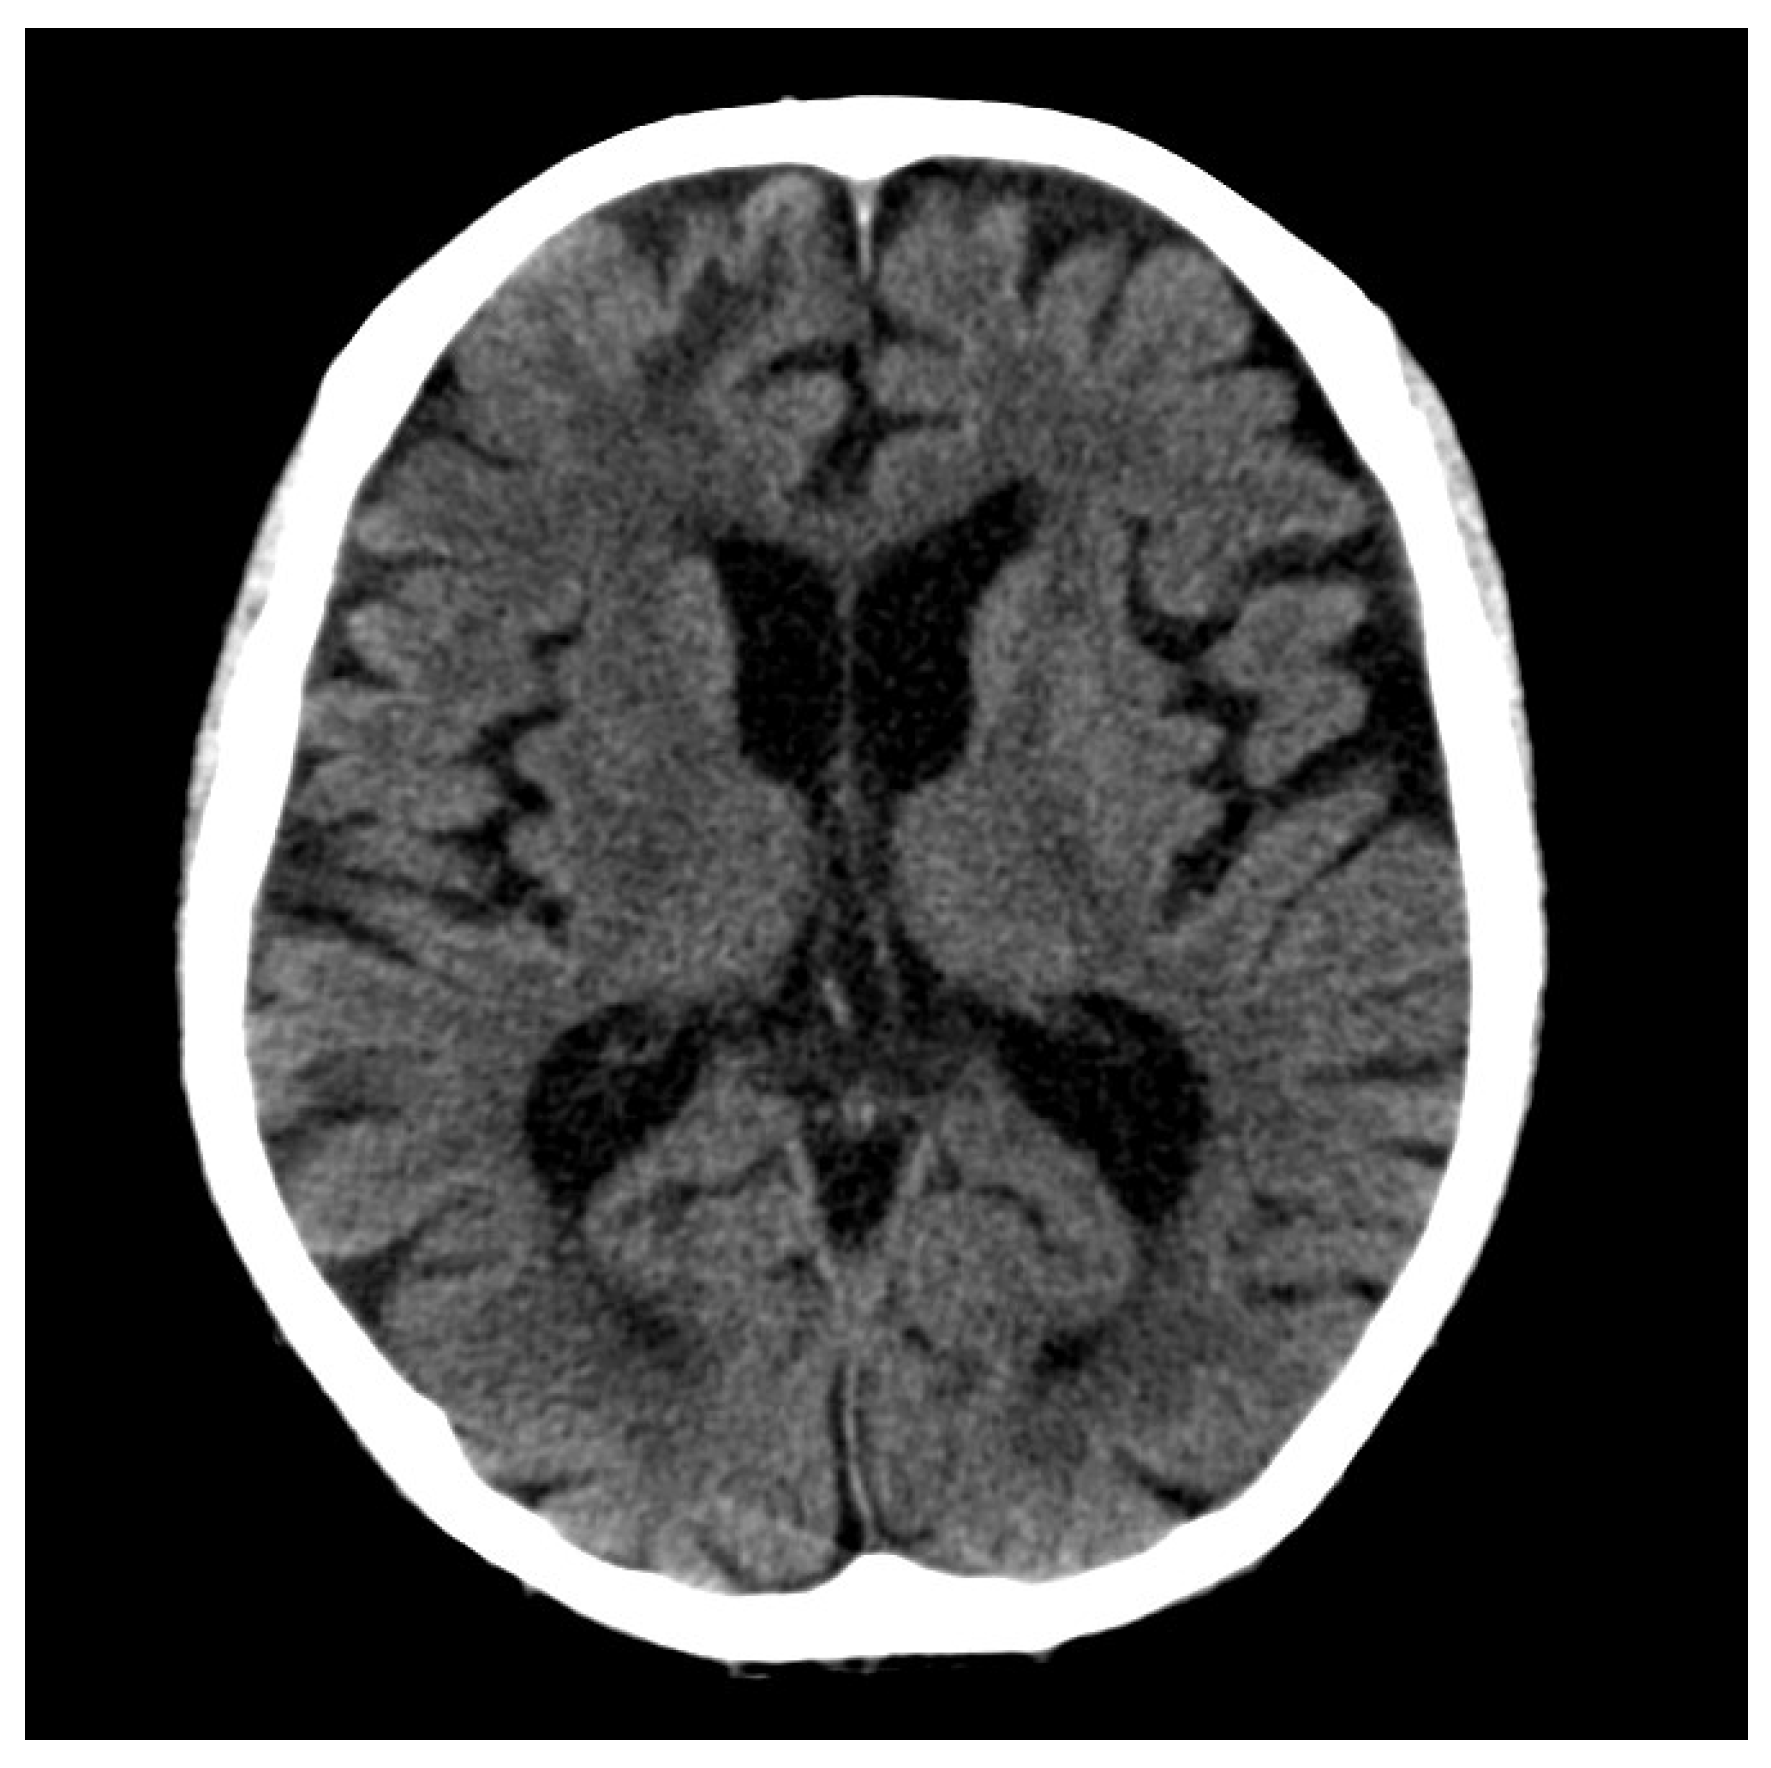

2. Case Presentation